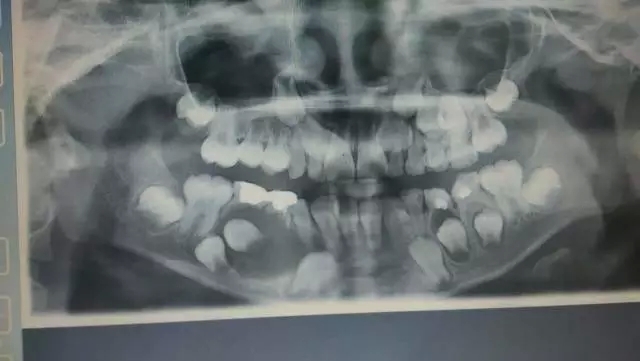

經(jīng)全景片檢查示:右側下頜骨體部可見一類圓型單囊透射陰影,含44恒牙牙胚,頜骨邊緣光滑,邊界清晰,囊壁累及乳牙及45恒牙,鄰界右下牙槽神經(jīng)血管,診斷為“右下頜骨囊腫(含牙囊腫)”。

全景片示:右下頜巨大頜骨囊腫,鄰界右下頜神經(jīng)血管